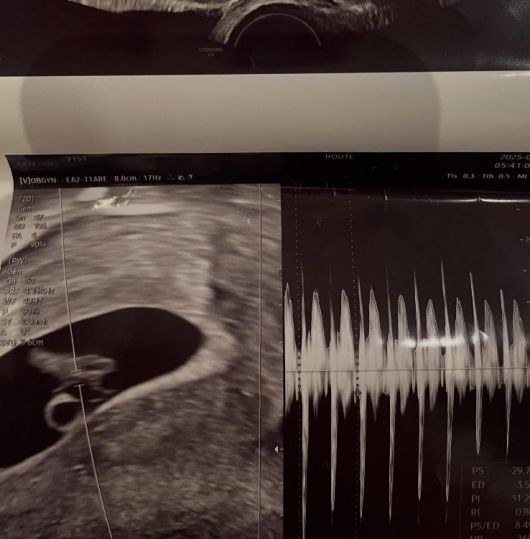

사진에는 서민재의 것으로 추정되는 초음파와 함께, 남자친구와 다정하게 붙어 셀카를 찍고 있는 모습이 담겼다.